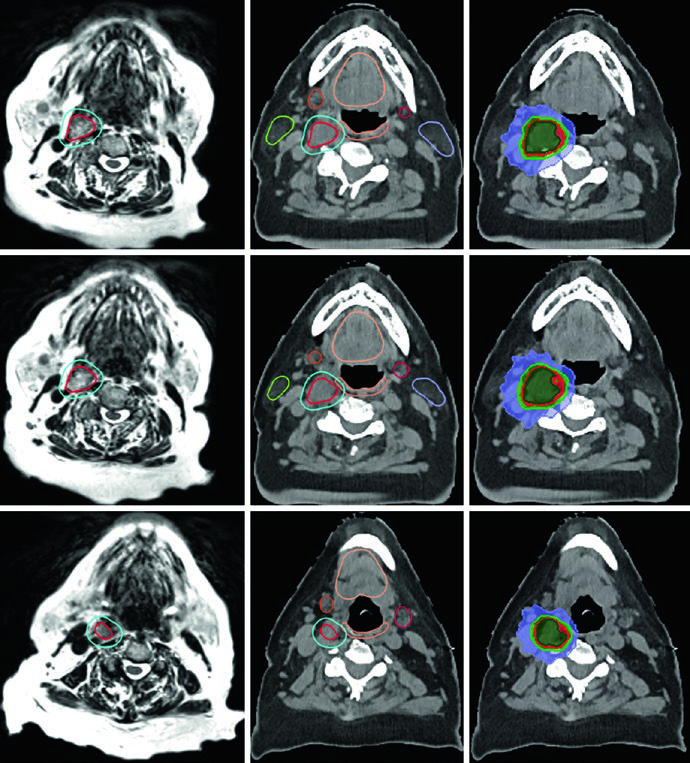

A Figura 29.14 mostra um tumor glômico carotídeo que separa as artérias carótidas interna e externa. O GTV (vermelho) foi delineado em RM T2 SPACE co-registrada à TC, com expansão de 3 mm para PTV. O paciente recebeu 25 Gy em 5 frações com linhas de isodose de prescrição (25 Gy), 110% (27,5 Gy), 80% (20 Gy) e 50% (12,5 Gy), com preservação de parótidas, glândulas submandibulares, cavidade oral e parede orofaríngea.

O caso da Figura 29.15 demonstra um cenário mais complexo: tumor glômico recorrente no bulbo jugular esquerdo após embolização e ressecção, tratado com 54 Gy em 30 frações. O GTV foi gerado co-registrando imagens de RM do diagnóstico inicial e da recorrência, incluindo a extensão original da doença, alterações pós-operatórias, leito tumoral e doença recorrente com cobertura até a base do crânio. Margem de 0,3 cm definiu o PTV. Múltiplos OARs — tronco encefálico, mandíbula, parótidas, medula com PRV, parede orofaríngea, cavidade oral e lábios — foram cuidadosamente delineados.